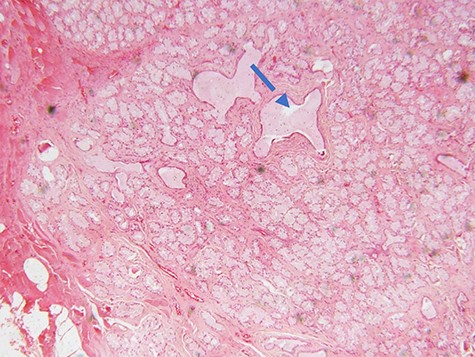

Microscopic examination of the excisional biopsy materials showed a lesion composed of proliferating acinar (Fig. 1) with lining epithelium composed of columnar to cuboidal mucin-secreting cells showing no atypia (Fig. 2). The lesion was divided by fibrous septae to form lobules (Fig. 3). There was a focal area that was showing element of moderate dysplastic changes with element of obliterating tubules, increased hyperchromasia and moderate pleomorphism (Fig. 4). The ratio of duct-to-acini was maintained. Sparse chronic inflammatory infiltrate composed of mainly lymphocytes was present. Neither mitoses nor necrosis were present. The surgical margins were free of the lesion. This confirmed the histopathological diagnosis of Bartholin’s gland hyperplasia with dysplastic changes. After a period of 1 month she was called for clinical evaluation. Healing of the surgical scar was complete and she reported no discomfort or dyspareunia during sexual intercourse.

photomicrograph of haematoxylin and eosin (H and E) stained tissue section showing a lobulated mass composed of proliferating acini and some cystically dilated tubules with inspissation of pinkish proteinaceous secretions (arrow) (×40 magnification)